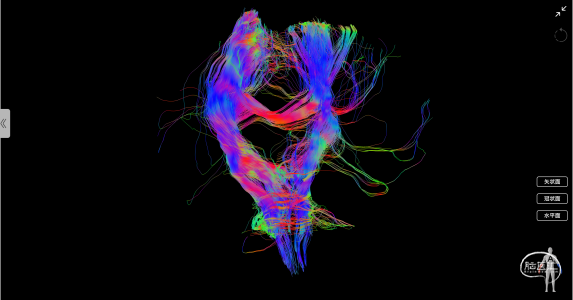

术后使用Nura Surigical脑网络重建分析显示:中央执行网络及皮质脊髓束较术前变化不大

图4:术前术后重建的中央执行网络对比(左侧为术前;右侧为术后)

图5:术前术后重建的皮质脊髓束对比(左侧为术前;右侧为术后)